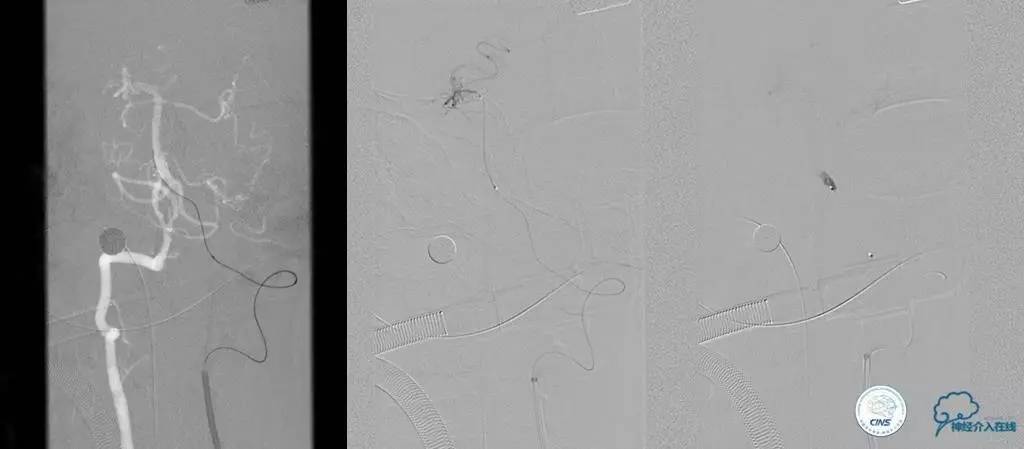

▼术前DSA

▼术中DSA

▼术后DSA